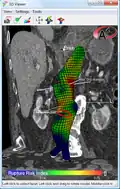

An aneurysm ruptures if the mechanical stress (tension per area) exceeds the local wall strength; consequently, peak wall stress (PWS),[32] mean wall stress (MWS),[33] and peak wall rupture risk (PWRR)[34] are more reliable parameters than diameter to assess AAA rupture risk. Medical software allows computing these rupture risk indices from standard clinical CT data and provides a patient-specific AAA rupture risk diagnosis.[35][36][37] This type of biomechanical approach has been shown to accurately predict the location of AAA rupture.[36][37][38]

Biomechanical AAA rupture risk prediction -